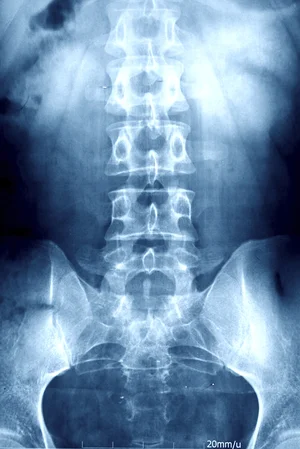

X-Ray/ MRI

X-rays provide information that will assist our Team of Doctors in planning your treatment. X-rays can reveal fractures, spinal misalignment, joint and bone disease and other factors regarding your health status.

Dr. Aramian will send any patient that needs an MRI and X-ray before receiving treatment so that we can give our patients the care they need.